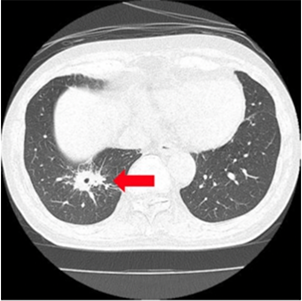

マイコプラズマ肺炎

小児の長引く咳は、マイコプラズマ肺炎の場合があります。

非定型抗酸菌症

数か月続く咳では、非定型抗酸菌症の場合があります。

珍しい病気ですが治療が必要です。